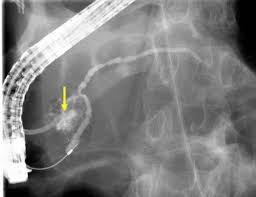

Coledocolitiasis Extracción de Cálculos

Los cálculos biliares son recolecciones de colesterol, pigmento biliar o una combinación de ambos, que pueden formarse en la vesícula biliar o dentro de los conductos biliares del hígado. El tipo más común de cálculos biliares es producto del colesterol. Los cálculos de colesterol se forman debido a un desequilibrio en la producción de colesterol o en la secreción de bilis.

El tratamiento para los cálculos biliares que obstruyen el conducto biliar común es la colangiopancreatografía retrógrada endoscópica (CPRE) o una intervención quirúrgica. La CPRE implica introducir una sonda fina y flexible por la boca hasta llegar al duodeno, donde se la utiliza para evaluar el conducto biliar común o el conducto pancreático.